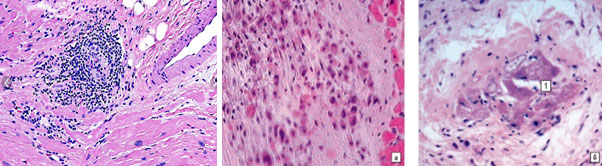

Кандидатными триггерами ревматических гранулём и аутоиммунного ответа могут быть продукты дезорганизации соединительной ткани, в частности, очаги фибриноидного некроза. На рис. 10 представлена патоморфологическая картина ревматоидного узелка при ревматоидном артрите (слева), а также гранулёмы в миокарде при ревматической лихорадке. Видно, что мононуклеарные клетки, прежде всего, клетки макрофагально-моноцитарного ряда и лимфоциты в составе КВИ, четко располагаются вокруг очагов фибриноидного некроза.

Рис. 10. Слева ревматоидный узелок (Х100). Справа два снимка гранулёмы в миокарде при ревматической лихорадке. В центре гранулём продукты распада основного вещества соединительной ткани, вокруг мононуклеарная инфильтрация (Х200), по материалам [14]

Сказанное иллюстрируется картиной гранулёмы Ашоффа-Талалаева при ревматическом миокардите, представленной на рис. 11, где определяются крупные гиперхромные (активированные) макрофаги, а также лимфоциты, располагающиеся вокруг и в очагах фибриноидного некроза.

Рис. 11. Гранулёма Ашоффа-Талалаева при ревматическом миокардите. Видны крупные гиперхромные макрофаги, лимфоциты, очаги фибриноидного некроза (Х200), по материалам [14]